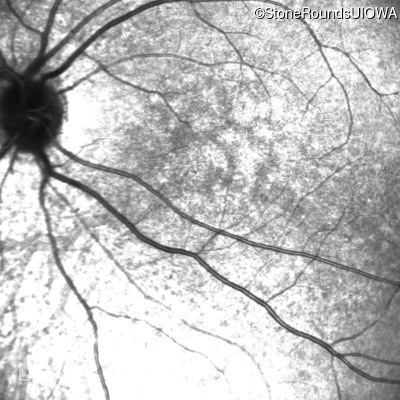

Infrared Fundus Photograph - Right - 5/200

Exemplar